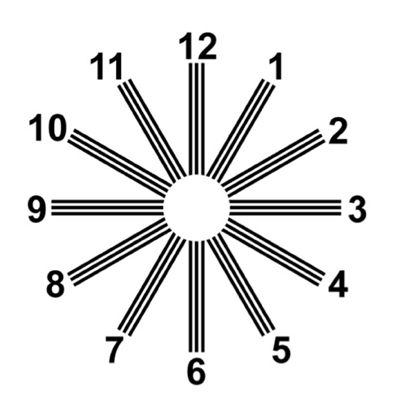

A:判斷自己有沒有散光,最簡單的方法是使用散光表來測試。散光表是一種簡單、方便的方法,但是它的準確度不是特別精確。在配鏡的情況下一般再用裂隙法,或者是交叉圓柱鏡法來精調散光的度數。散光表在網上可以看到,它類似於鐘錶的盤面,有12個數字。各個鏡線……